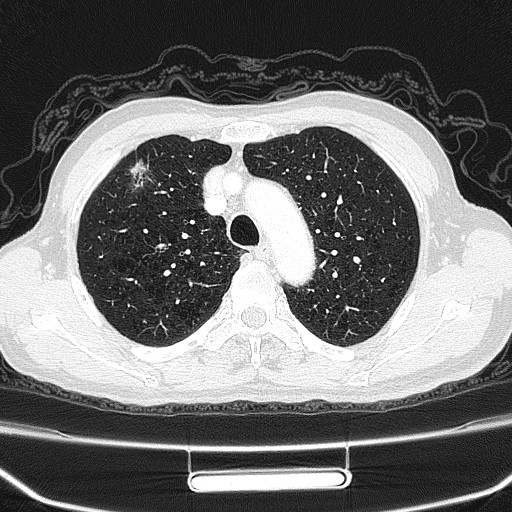

肺泡壁非常薄,里面充满空气,CT的X线轻松穿透后形成黑色的图像,肺纹理清楚,没有增粗、紊乱、阴影和结节。

从胸部CT上看,肺部磨玻璃病变表现为边界清楚或不清楚的云雾状的圆形、类圆形病灶或不规则密度增高影,但病变密度不足以掩盖其中走行的血管和支气管影,看上去像磨玻璃,俗称“磨玻璃影”,这是由于肺部病变时X线不容易穿透造成,只是影像学上的一种客观描述,不代表疾病本身或预示病情的走向。